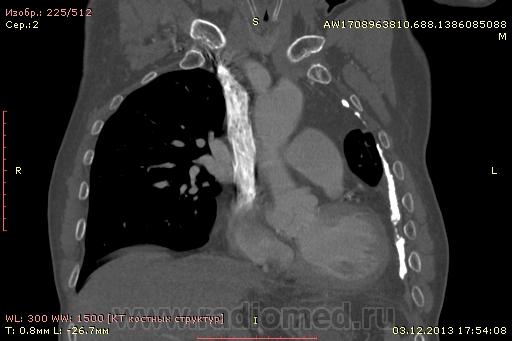

Доброго времени суток уважаемые форумчани! :)Провели исследование КТ грудной клетки с контрастированием, для выявления аневризмы грудного отдела аорты. В результате увидели это:

Говорил с врачом, у больного был плеврит неизвестной давности.

??? Аневризму честно не вижу (мало опыта в определении аневризм). Тромбоз в бассейне верхней полой вены. В левом легком обызвествленные плевральные шварты? как исход осумкованного плеврита неизвестной давности?

на VRT-реконструкции. плотность до + 1000 HU. видел такое как посттуберкулезные обызвествления плевры, надо завтра ещё раз поговорить с лечащим врачом, может ошиблись

намерил аорту, всё таки есть аневризматическое расширение луковицы

Ребята, вы что, какая жидкость? Чистая известь, посмотрите в костном окне. Отставить натив (в данном случае, хотя для аневризм он обычно нужен). Отставить тромбоз верхней полой вены (потоковые артефакты, не дело вены в артериальную фазу оценивать). Отставить аневризму  аорты, поперчник восходящего отдела на уровне легочного ствола 42мм. А вот легочная гипертензия, здравствуй: поперечник легочного ствола - 37мм, ПЛА - 25мм, ЛЛА - 25мм, НАо - 25-34мм.

Нет ТЭЛА. Фиброторакс слева.

Для справки: холестериновые камни имеют плотность менее 100 ед.Н. Имеющаяся хренотень в левом гемитораксе имеет плотность больше костной, до 1500 ед.Н. Вопрос: какая химико-физико-биологическая реакция может способствовать превращению мягинькаво холестерина в термоядерную плевральную лепёшку?)

В анамнезе перенёс туберкулёз неизвестной давности.